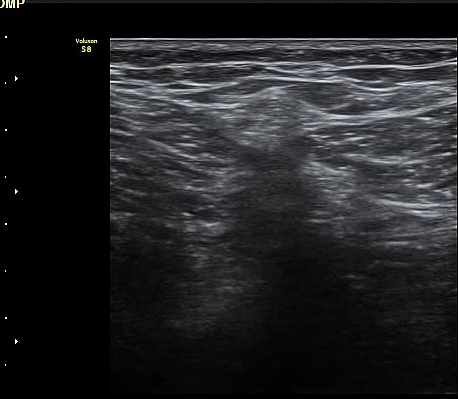

ŽÃËÀÚ¸¦ ¸»´ÜÀ¸·Î À̵¿ÇÏ´Ï º¹Àç½Å°æÀÌ ½½°³°ñÇϰ¡Áö¿Í  ºÀ°ø°¡Áö(sartorial branch)·Î

°¥¶óÁö´Â °ÍÀÌ °üÂûµÇ°í(»çÁø 3, 4, 5) µ¿¿µ»ó È­¸éÀ¸·Î º¸¸é ´õ¿í ¶Ñ·ÈÇÏ´Ù(÷ºÎ ÆÄÀÏ 1)